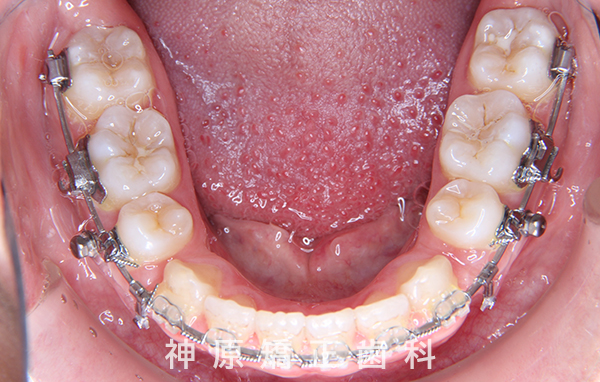

マルチブラケット装着1年後